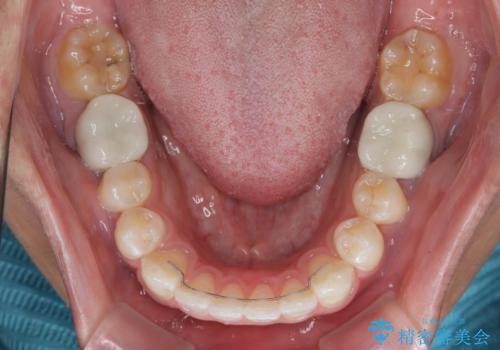

矯正治療後は、奥歯の銀歯をセラミッククラウンにて補綴治療を行うこととしました。

あっという間に歯列が整い、目立っていた銀歯もなくなり、清潔感のある口元になりました。